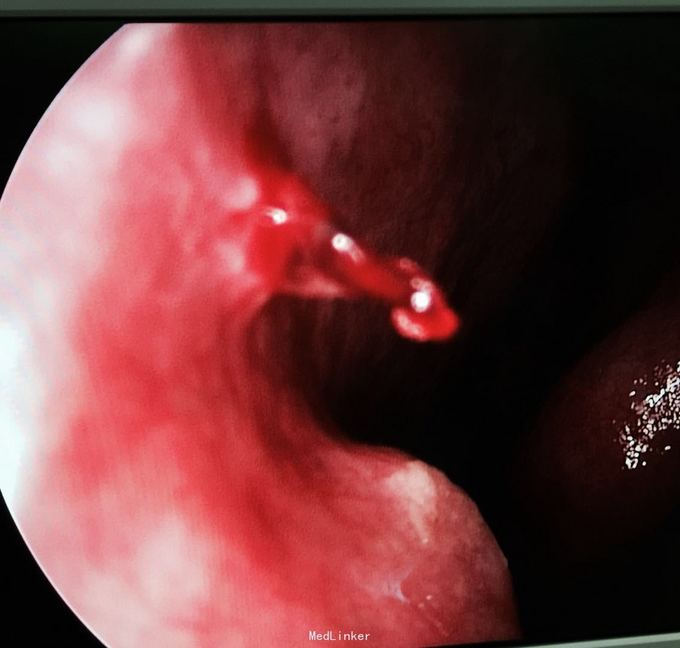

一般情况好,左鼻腔Little 's 区见红色肉芽样新生物,触之易出血,约米粒大小,质软。见图 肝功能、肾功能,血常规,出凝血时间均正常。

诊断:鼻中隔新生物(血管瘤可能) 处理:局部麻醉鼻内镜下行新生物摘除,双极电凝止血。 术后病理:肉芽性血管瘤